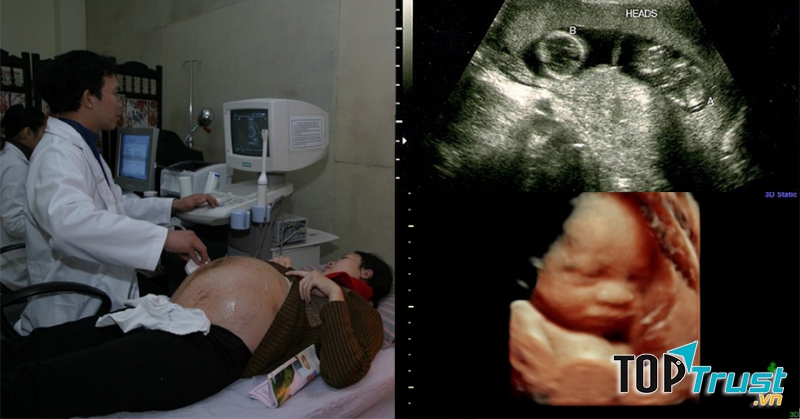

- Siêu âm màu doppler, 3D - 4D, đo độ mờ da gáy.

- 01 máy siêu âm màu 3D - 4D Doppler

- 01 máy siêu âm